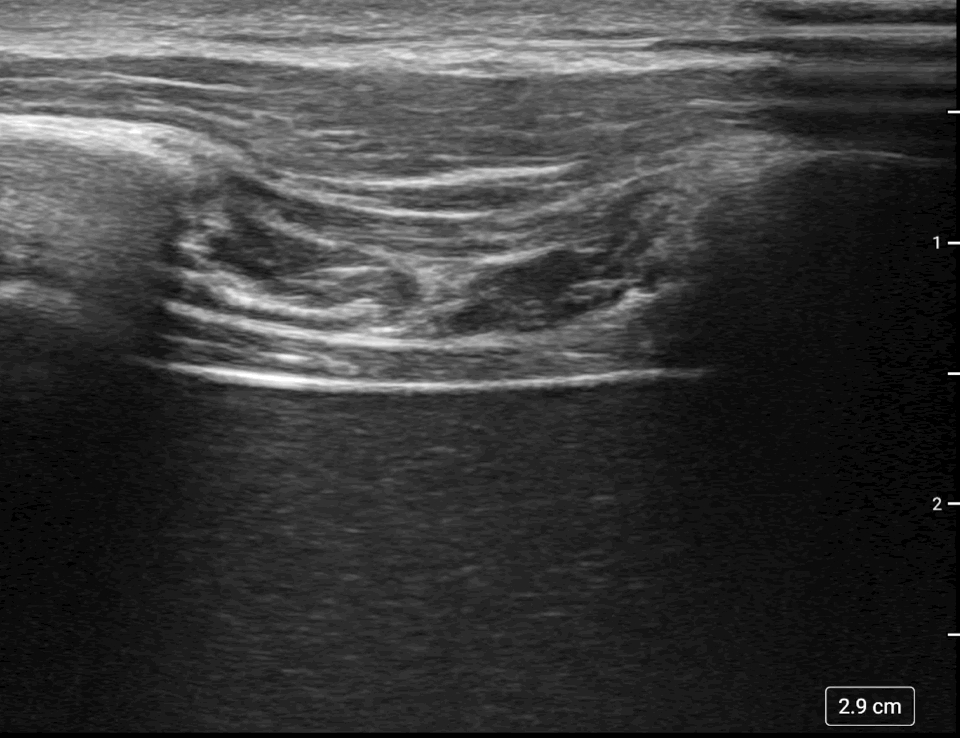

: – Thickening Fraction (TF) of the Zone of Apposition (ZOA)

The Thickening Fraction (TF) method evaluates the contractile activity of the diaphragm by measuring its thickness during the respiratory cycle. It is particularly useful in critically ill or mechanically ventilated patients where excursion alone may be misleading.

πŸ”Ή Probe

Linear probe (high frequency, 8–18 MHz)

πŸ”Ή Patient Position

Upright or semi-recumbent position is ideal for optimal image quality.

πŸ”Ή Probe Placement

Place the probe in a coronal plane between the 7th and 9th intercostal spaces, between the anterior and midaxillary lines.

πŸ”Ή Image Acquisition

The diaphragm appears as a three-layered structure just below the chest wall:

• A dark (non-echogenic) muscular layer

• Sandwiched between two bright echogenic membranes:

• Pleura (anterior)

• Peritoneum (posterior)

Measure the thickness of the diaphragm at the end of expiration and again at the end of inspiration (preferably during a vital capacity maneuver).

πŸ”’ Calculation

Thickening Fraction (TF) =

(Thickness at end-inspiration βˆ’ Thickness at end-expiration) / Thickness at end-expiration Γ— 100

πŸ“ Clinical Considerations

• TF is especially useful in patients on mechanical ventilation, where passive motion can mimic active excursion.

• TF provides a direct assessment of diaphragm muscle activity and contractility.

• TF less than 20% suggests dysfunction; close to 0% suggests paralysis.